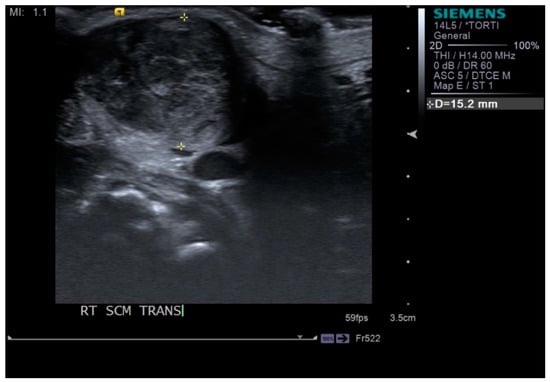

| SCM thickness (mm) | Initial | 15.64 ± 5.24 | 5.76 ± 1.62 | <0.001 * |

| After 3 months | 11.36 ± 5.71 | 6.61 ± 1.06 | 0.001 * | |

| SCM thickness (mm) | 15.64 ± 5.24 | 11.36 ± 5.71 | <0.001 * |